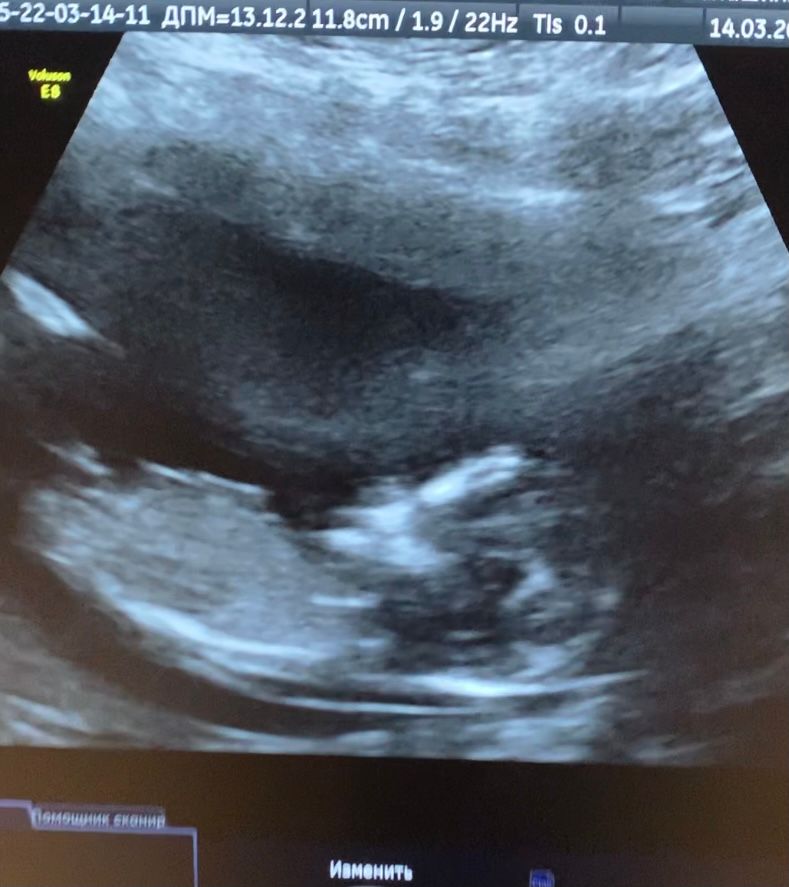

Мальчик или девочка? Фото 13недель

14.03.2022

Фото не качественное. Но даже на таком фото кажется что девочка

Бугорок вроде прямо расположен , значит, девочка.